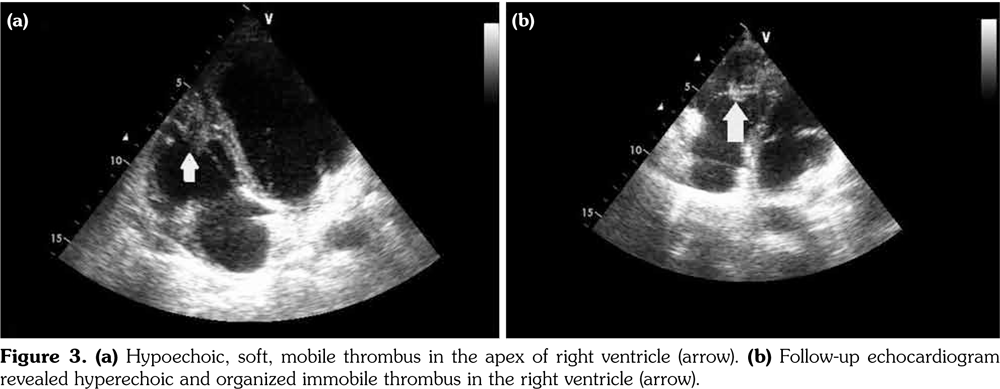

Chest X-ray showed left parahilar opacity (Figure 1). Pulmonary computed tomography (CT) angiogram revealed PAA with thrombus (Figure 2a). Bronchoscopy revealed no origin of bleeding. Echocardiography demonstrated mobile thrombus in the right ventricle (Figure 3a). Blood and urine cultures were sterile. Venereal Disease Research Laboratory test, tuberculosis tests, human immunodeficiency virus serology, antiphospholipid antibodies, anti-nuclear antibodies, and anti-neutrophil cytoplasmic antibodies were negative. Hereditary coagulation thrombophilic factors were normal.